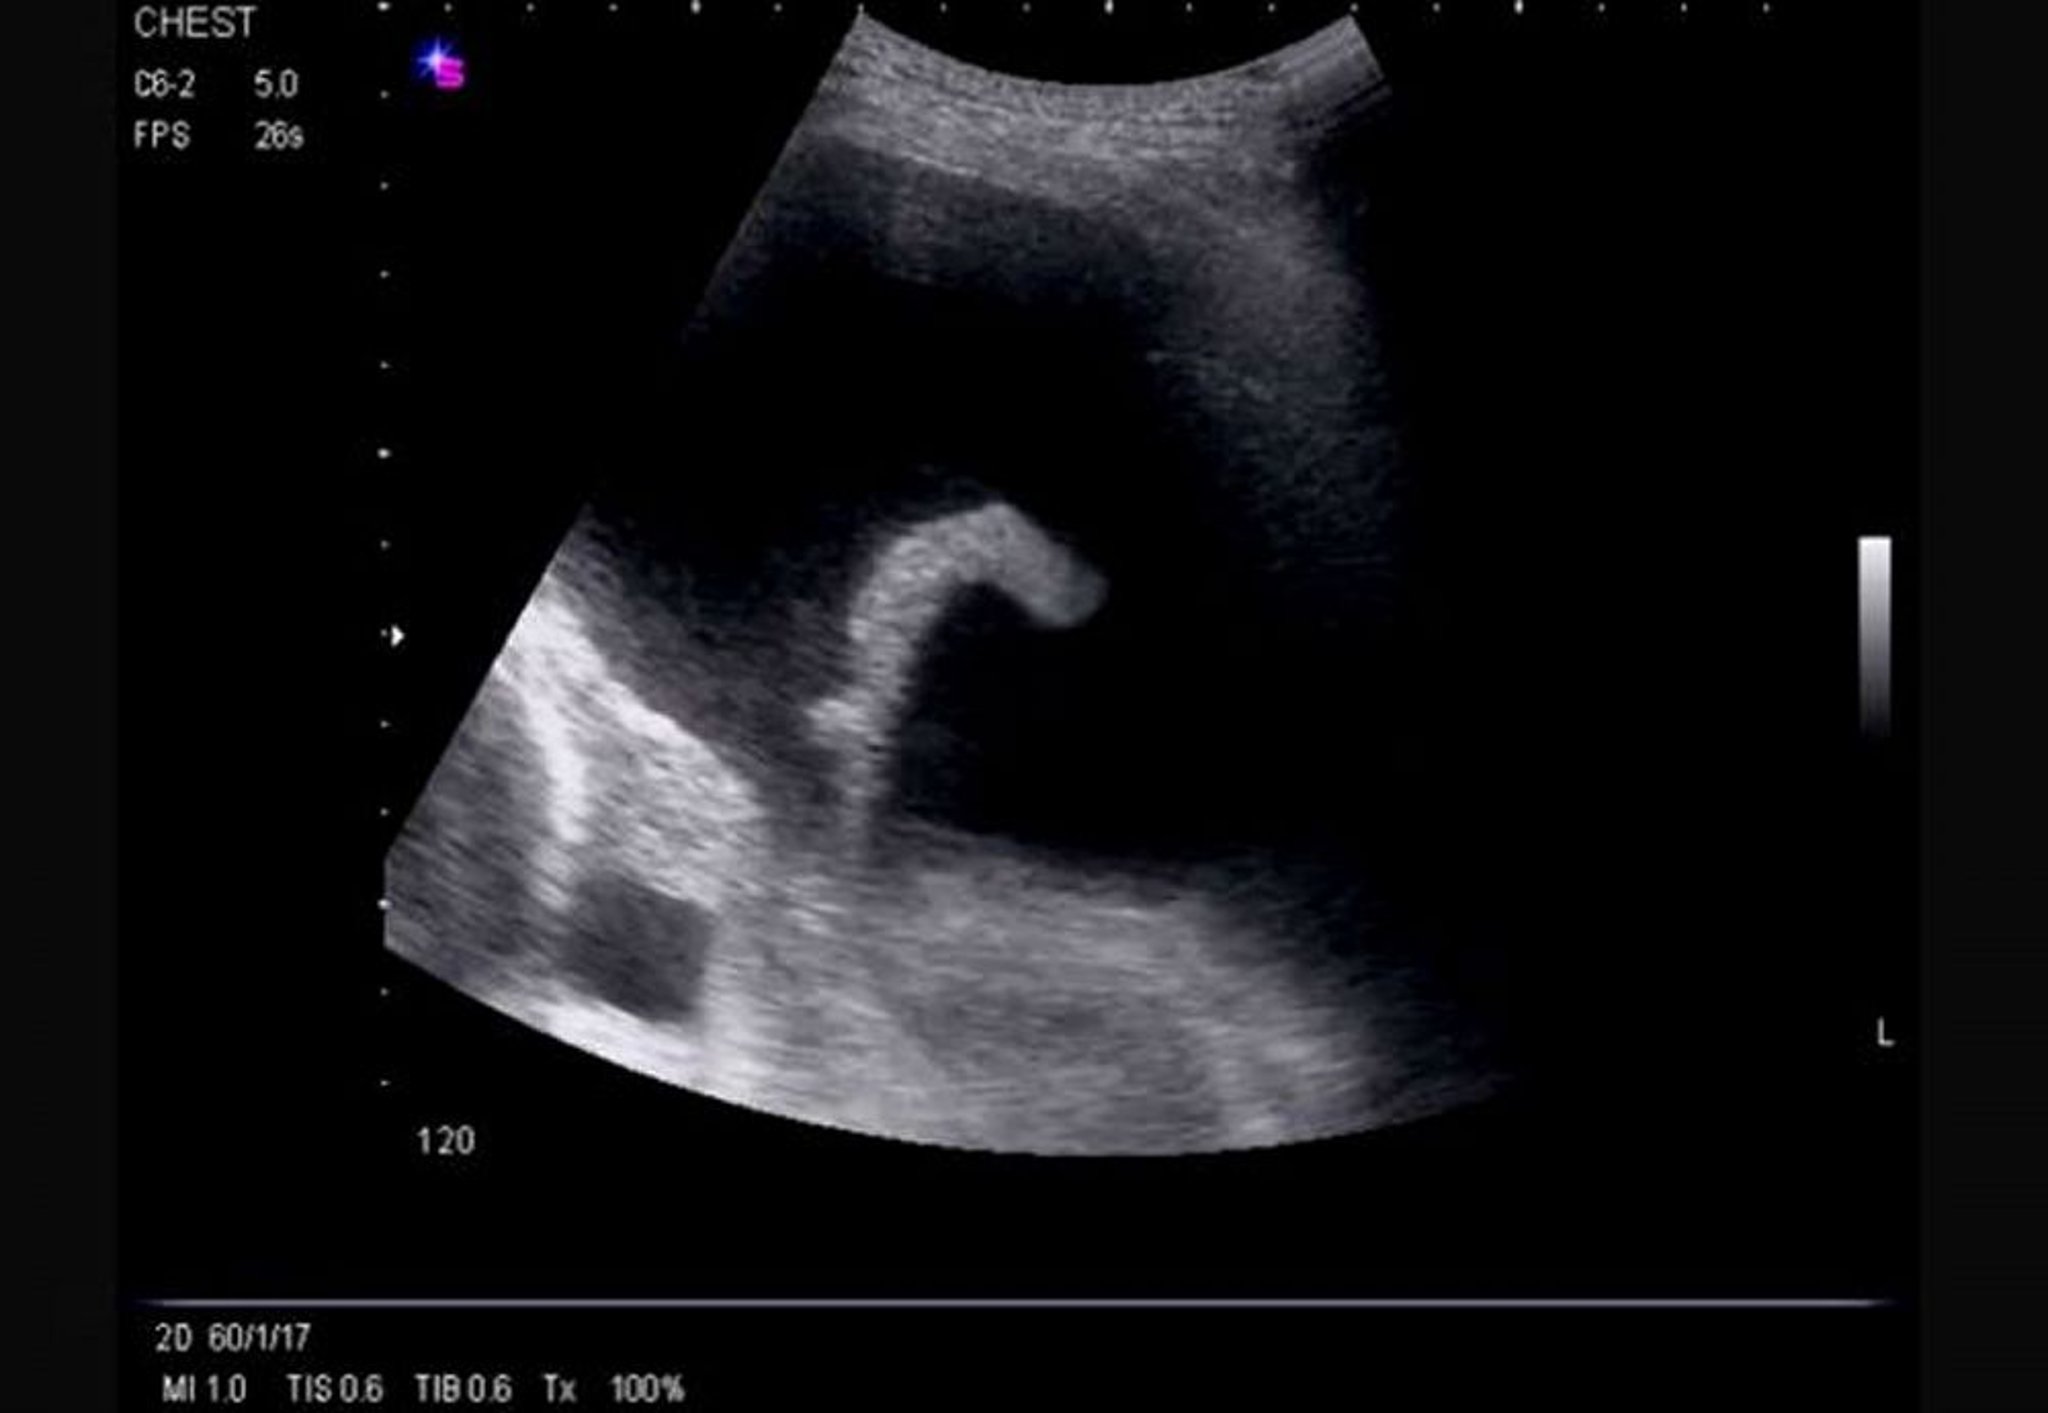

Thoracic ultrasound is considered standard of care for diagnosis of pleural effusion and is performed and interpreted by physicians at the bedside. It is highly accurate for the detection of small volumes of pleural fluid and provides additional diagnostic information (eg, the presence of septation, pleural thickening).